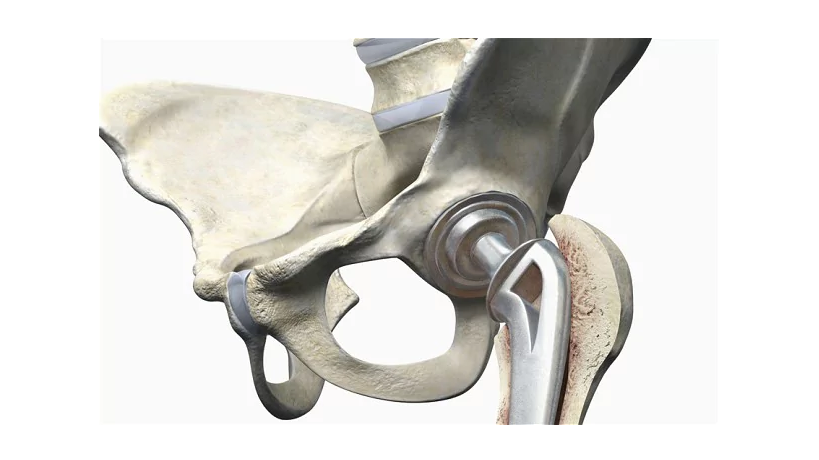

ICON cavity is a cementless ideal hemisphere with a layer of porous hydroxylapatite applied, which provides the fastest adaptation in the bone tissue and thereby its stability and stability of the prosthesis.

The ICON joint surface prosthesis is made from a high-alloy cobalt-chromium-molybdenum alloy with a high carbon content according to ISO 5832-4 of the German industry standard.

ICON PCB is produced by a single casting without subsequent heat treatment, which keeps a high content of planar block carbides, which ensure the highest degree of hardness of surfaces and its wear resistance.

The illustration shows a transverse rupture of the outer surface of the cavity. The spherical surface structure creates conditions for the biological integration of the acetabulum into the bone weave and its optimal primary stability. Clearly visible tree-like carbide blocks and a grain-free border that is achieved with a single casting.

Four small anti-rotation wings on the cavity provide the primary, as well as in the natural cavity, stability of the implant.

The ICON cavity is additionally layered additionally layer by layer approximately 65 μm hydroxylapatite (GAP), which promotes the best integration of the implant in the bone and provides secondary stability (GAP is much softer than CoCr, and during dissolution eliminates the emergence of a connective tissue capsule).

In this metal-metal friction pair, thanks to the high-quality polishing of the contacting surfaces, an optimal joint gap is created which, on the one hand, ensures the penetration of the liquid and thereby creates a hydrostatic lubricant effect, and on the other hand prevents wedging. Thus, simultaneous reduction of adhesion and friction, contacting surfaces, provides the most long-term function of the prosthesis.